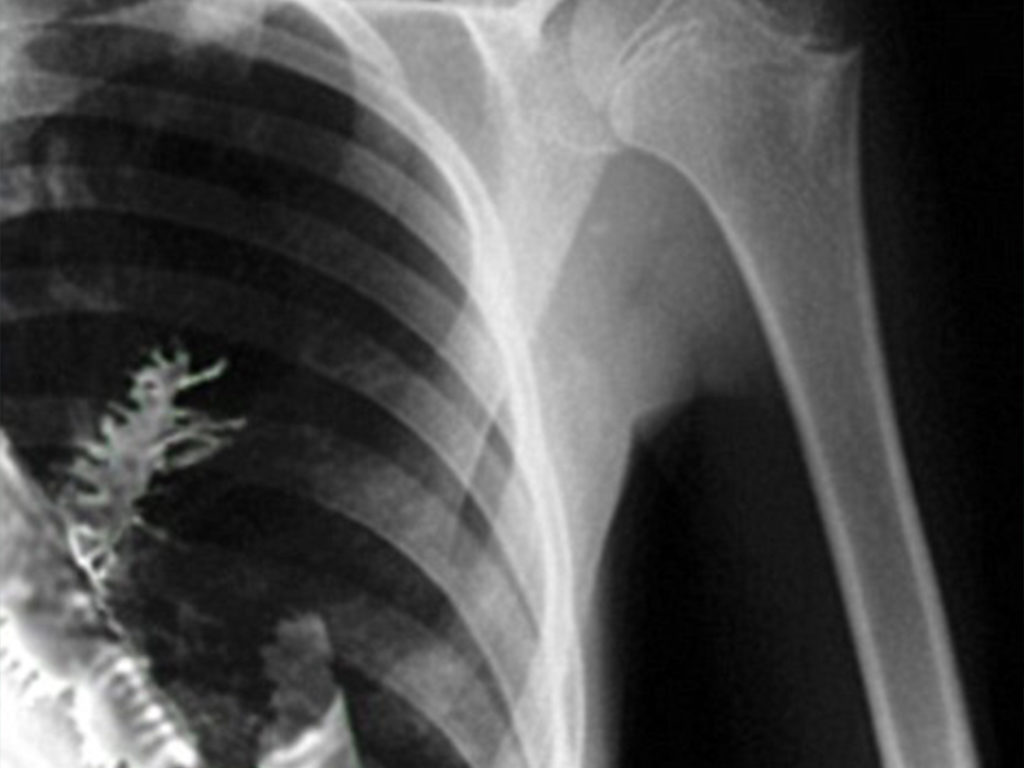

Artyom Sidorkin from Russia was suffering from chest pain and doctors believed it was a tumor. But when they performed surgery on him, they found a 2-inch-long fir tree growing in his lung. They assumed he inhaled a fir seed while he was in the woods training in the army.